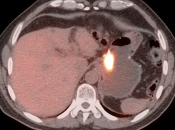

Normal FDG uptake involving the stomach can be extremely variable. It is not uncommon to see diffuse intense uptake throughout the entire stomach or intense uptake limited to only a segment of the stomach (fundus, body or antrum).

• Focal or regional hypermetabolic activity is accompanied by at least the suggestion of associated wall thickening (often difficult to assess if the patient’s stomach is suboptimally distended with water or oral contrast);

• Uptake is extremely focal (more likely to represent malignancy or ulcer);

• Focal/segmental uptake is extremely intense.